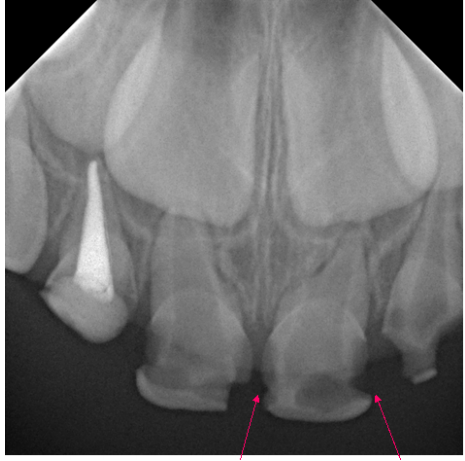

65.下圖箭頭所指之帶狀的放射線不透過性(radiopaque)影像是: (A)mylohyoid ridge (B)external oblique ridge (C)mental ridge (D)superior wall of mandibular canal

66. 下圖紅色箭頭指示的地方最可能的診斷為:

(A)Rampant caries (B)Periodontal disease (C)Concrescence (D)Fracture